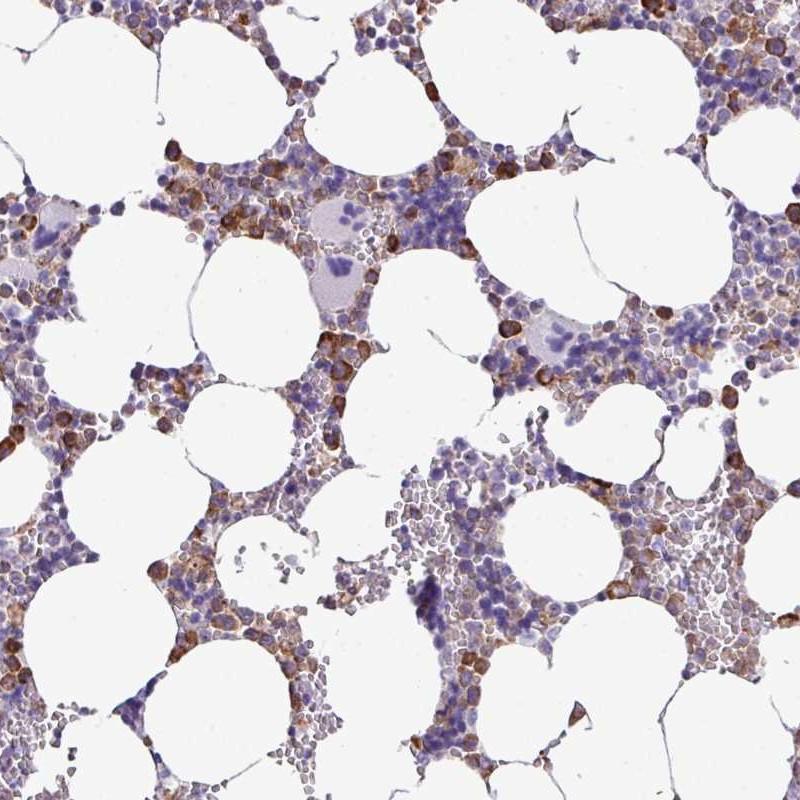

Immunohistochemical staining of human bone marrow shows distinct cytoplasmic positivity in subsets of hematopoietic cells.